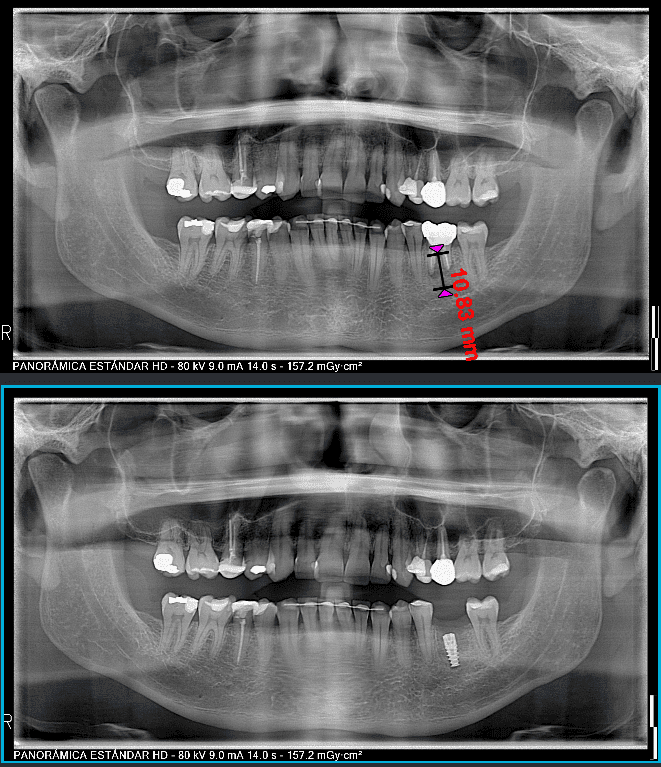

•  CBCT (TAC dental) para medir milímetro a milímetro tu hueso y estructuras anatómicas en los tres ejes de la zona a tratar (3D).

•  Plan digital del número, posición y angulación de los implantes.